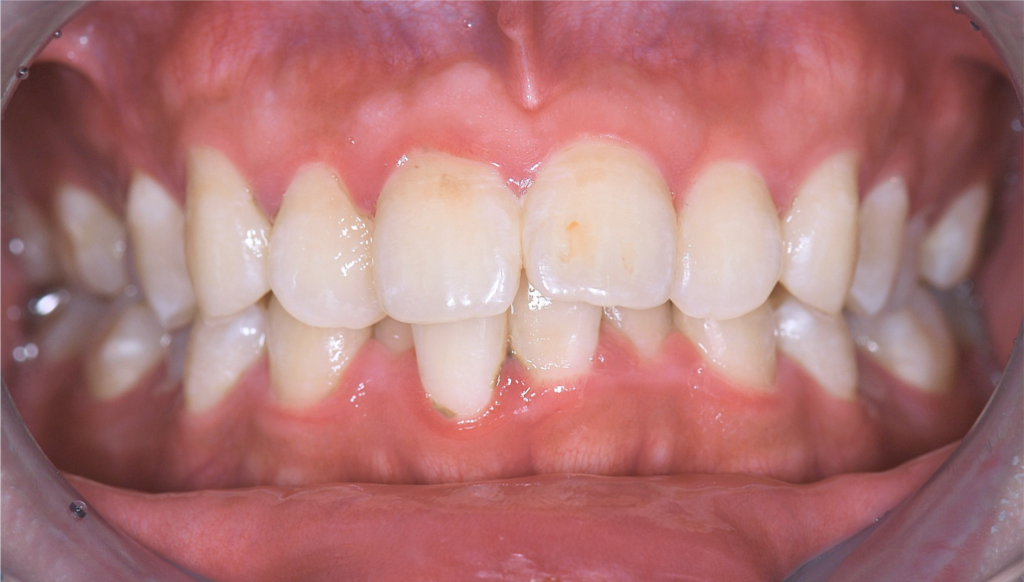

上下ともに狭窄歯列、下顎前歯には叢生(歯のガタつき)、上顎前歯の突出感が認められました。

また、やや上の前歯が下の前歯に覆い被さり、噛み合わせが深い(ディープバイト)傾向もあり、奥歯への負担が強くかかる噛み合わせでした。